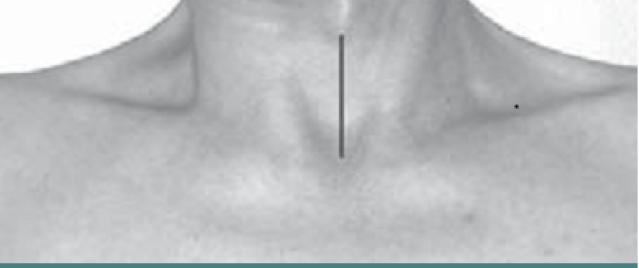

Larynx shifted relative to sternum

LATERAL SHIFT

Secondary to lateral flexion of the spine and flexion of the head in the opposite direction.

Line from Sternum to larynx